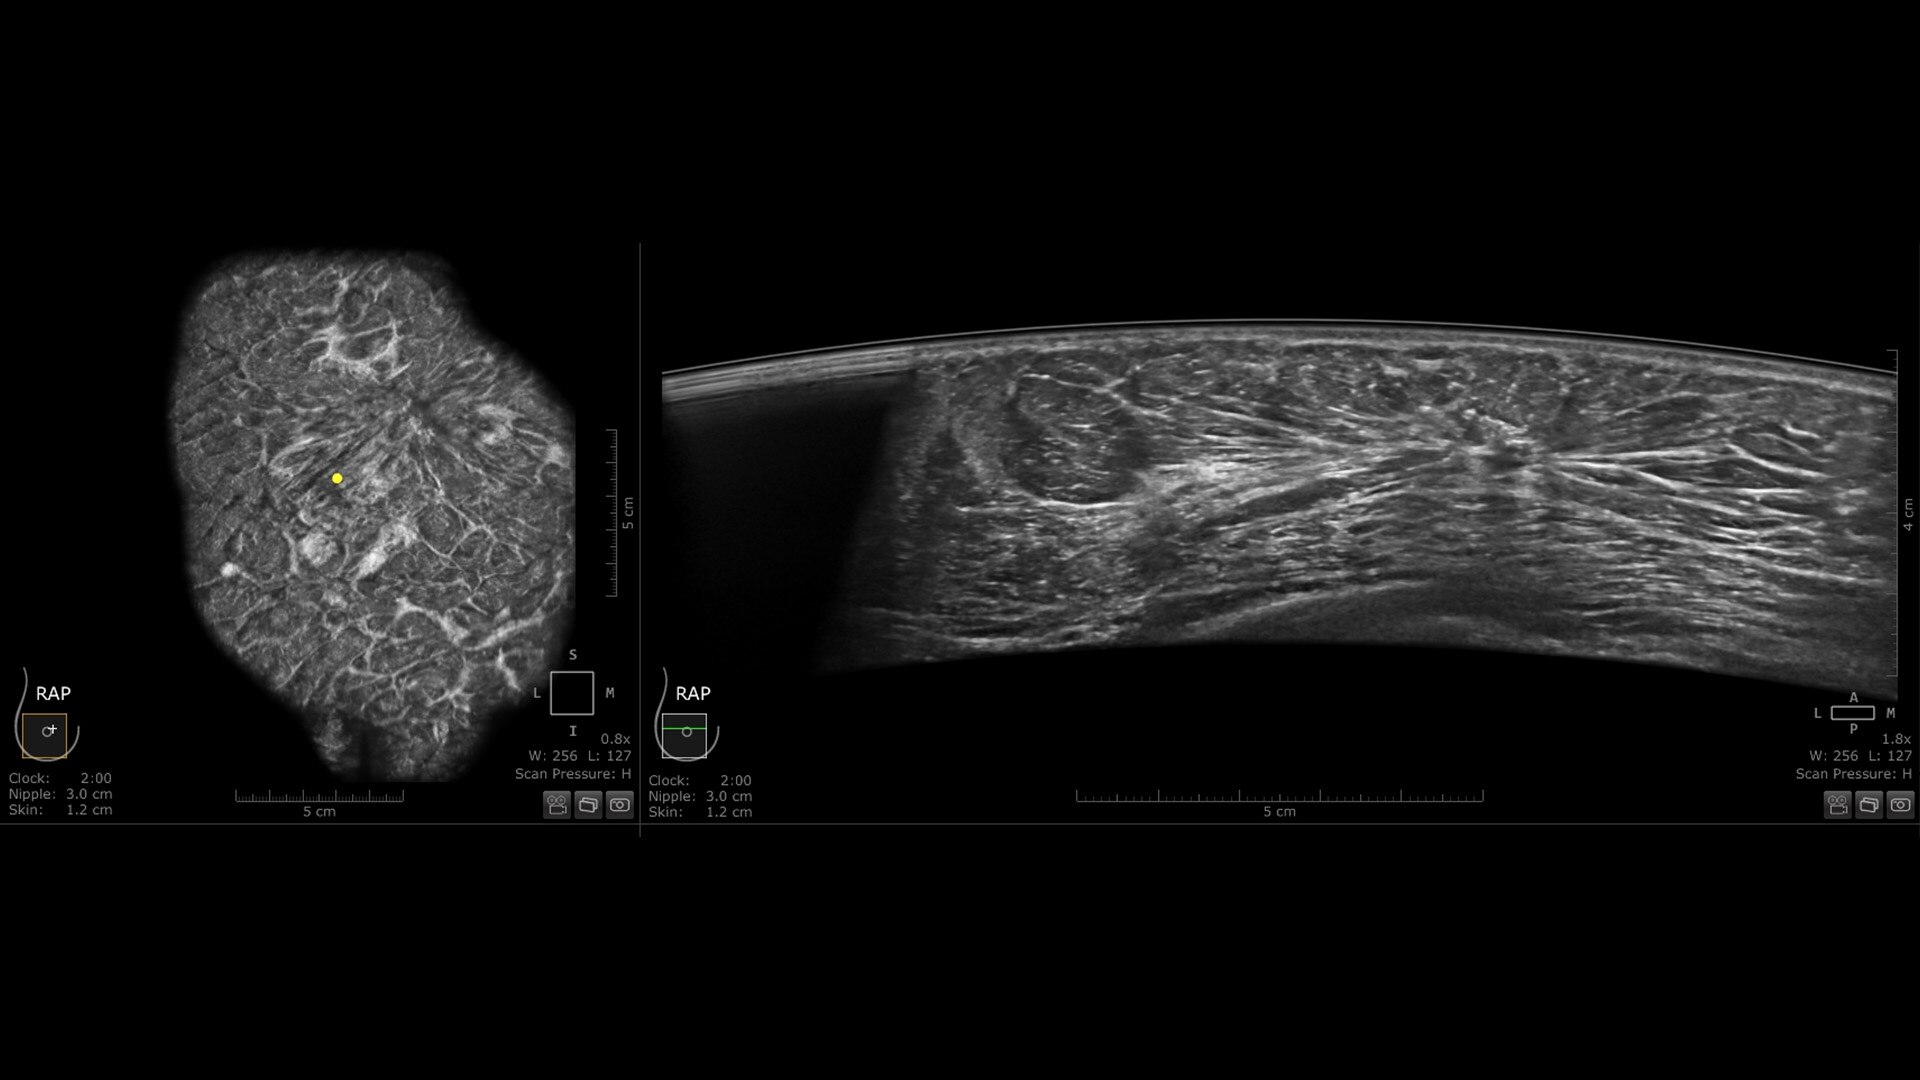

Centralized reading everywhere with the Invenia ABUS Viewer with AI Assistant

Invenia ABUS Viewer’s efficient workflow, with AI Assistant**, allows physicians to quickly review, interpret, and archive exams, even remotely.

• Decrease benign biopsies by up to 55% with Koios DS™ Breast

Exact lesion localization and double reading capability empower ABUS in early detection

Virtual rescans and multiplanar readings of the entire breast support case management